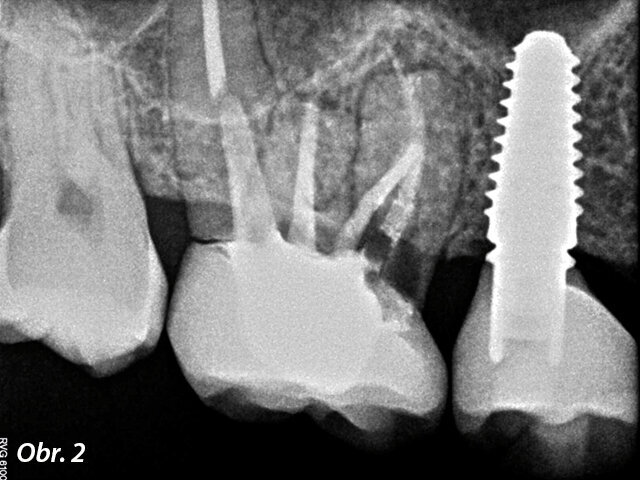

V listopadu roku 2017 se dostavila 39letá pacientka na vstupní vyšetření do White Clinic z důvodu bolesti zubu 16. Bylo provedeno klinické a radiografické vyšetření, včetně periapikálního snímku, CBCT skenu (Carestream 9600, Carestream Dental) a intra a extraorálních fotografií (obr. 1–3).

Při klinickém a radiografickém zhodnocení bylo zjištěno, že u zubu 16 byla přítomna cervikální resorpce v meziobukálním kořeni. Zvolený léčebný plán byl extrakce zubu a okamžité zavedení implantátu. Zub byl již v minulosti endodonticky přeléčen a ošetřen definitivní keramickou korunkou. Přestože je protokolem White Clinic zachovávání zubů, zub byl indikován k okamžité extrakci vzhledem ke stavu v dané situaci. Také z důvodu nedostatku času, nebyl náš digitální tým schopen vyrobit chirurgickou šablonu pro zavedení implantátu, proto zahrnoval léčebný plán chirurgickou fázi a digitální protetickou fázi.